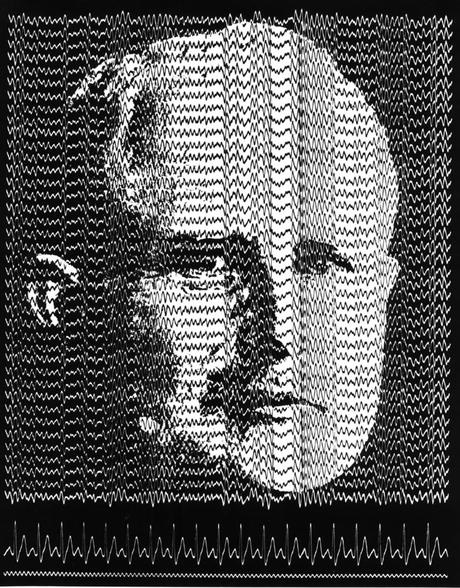

En vida, Berger había sido un médico y neuropsiquiatra ejemplar. En 1924 hizo una contribución clave a la ciencia y la medicina mundial: descubrió el electroencefalograma humano. Desde entonces, generaciones de científicos y médicos han usado esa técnica para estudiar el funcionamiento del cerebro, explorar trastornos neurológicos o determinar la muerte cerebral, una técnica “rompedora” que aún hoy sigue en uso. Las biografías de Berger dicen que fue un científico opuesto al régimen nazi y algunos apuntaron que su trágica muerte pudo estar relacionada con el horror de la guerra y el exterminio generado en Alemania. Un mártir de la ciencia.

Desde aquel accidente de juventud Berger se obsesionó con la telepatía y quiso buscar su explicación estudiando las señales que hacen funcionar el cerebro. Creía que el encéfalo era capaz de transmitir señales somos si fuera una radio cuyas ondas pueden ser captadas por otros cerebros que están en la misma frecuencia. Sus experimentos primero en pacientes a los que se había operado el cráneo y después en personas sanas incluida su hija desembocaron en un descubrimiento histórico. Berger fue el primero en grabar las señales eléctricas de un cerebro humano, el descubrimiento del electroencefalograma, en 1924. Consciente de la importancia de su hallazgo, el médico guardó su descubrimiento en secreto durante años, acumulando más y más datos hasta hacer un anuncio oficial en 1929.

La electroencefalografía fue recibida con una gélida oleada de escepticismo y no fue aceptada del todo hasta que otros científicos de Reino Unido y EEUU reprodujeron los resultados de Berger años después. Por su parte, Berger siguió haciendo hallazgos claves para la medicina y la ciencia, como la descripción de las ondas cerebrales que produce un cerebro sano o las que caracterizan a enfermedades como la epilepsia. Aunque la ciencia nunca le dio pruebas de que existiese la telepatía, Berger siguió creyendo en ella hasta casi el día de su muerte. En 1940, recordando aquel día en el que estuvo a punto de morir, escribió: “Este es un caso de telepatía espontánea en el que en un momento de peligro mortal, mientras contemplaba mi muerte segura, transmití mis pensamientos y mi hermana, que estaba muy unida a mí, actuó de receptora”. Para entonces Berger estaba jubilado, enfermo y, según sus biógrafos, asqueado por los nazis.